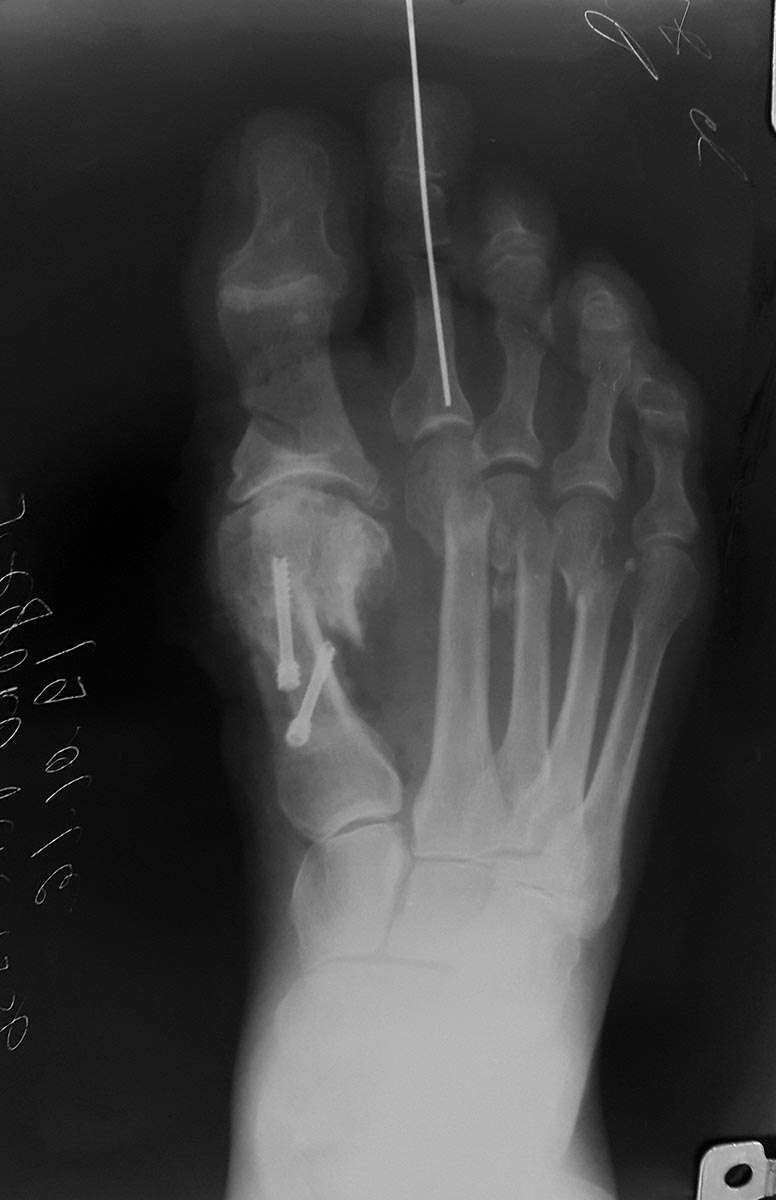

Сделал Обьем такой

scarf, Akin.

открыто вейль 2,3 с удлиннением длинного разгибателя 2 пальца, закрыто субкапитальная остеотомия 4 пальца.

хохман 2 фиксация спица 3 недели.

Оцените пожалуйста ситуацию. Вторые сутки отека нет все нормально со стопой.